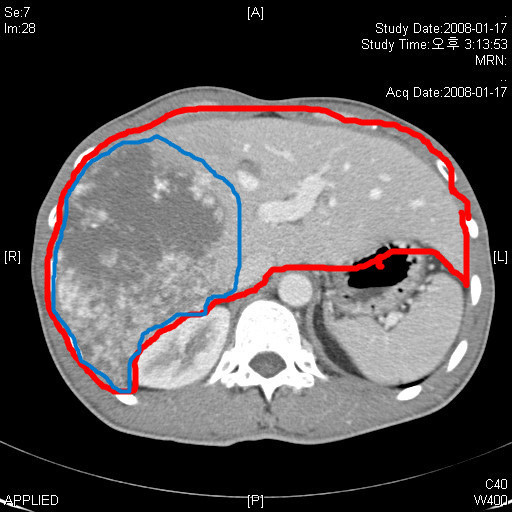

1) 초음파 검사, CT, MRI : 혈관종의 크기, 위치, 모양을 확인합니다.